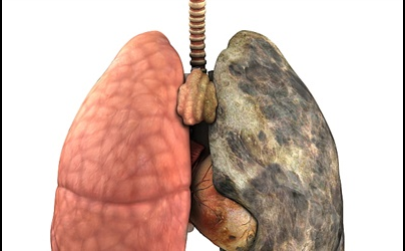

이번 기사에서는 폐암 초기 증상에 대해 자세히 정리해 알려 드리겠습니다 . 폐암은 국내암 사망률 1 위로, 과거에는 흡연이 폐암의 주된 원인 이었지만 , 현재는 비흡연 폐암 환자도 대폭 증가했습니다 . 폐암은 의학 기술로 발달하여 생존율이 높아지고 있습니다 . 폐암의 초기 증상은 무엇인가를 알아보겠습니다.